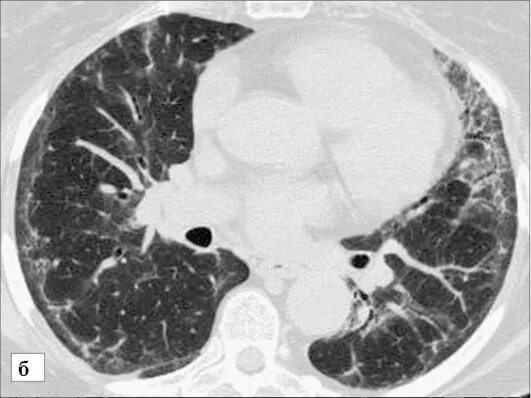

Гипостатические изменения кт